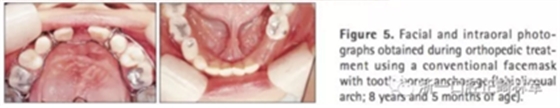

第二階段(圖5,6;表2)

面弓矯治包括在混合牙列及早期恒牙列的傳統(tǒng)牙支抗面弓及恒牙列的骨支抗面弓。由于患者曾行腭成形術,為了將矯治力傳遞到上頜骨,使用唇舌弓而不是快擴。8歲5月時開始用面弓聯(lián)合唇舌弓矯治(500g/邊,與合平面呈30°向下),持續(xù)3年6月?;颊吲宕鲿r間為12-14時/天。